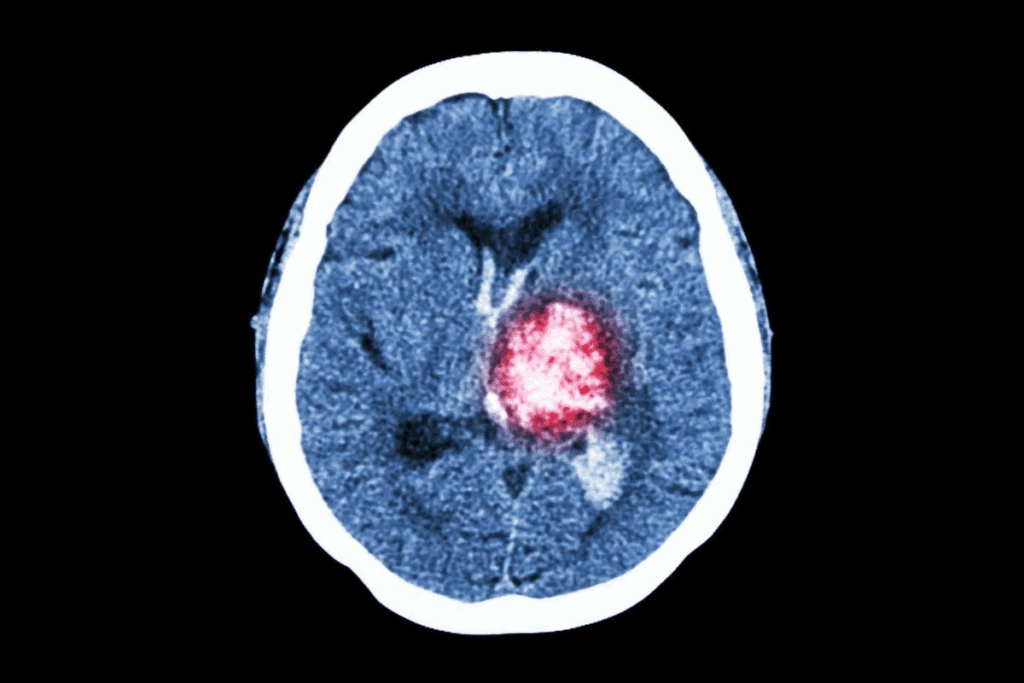

What Tumors Look Like on Imaging

On a CT scan, tumors show up as clear masses or lesions. They can be told apart by their density, edges, and how they change after contrast is added. Benign tumors have clear edges and a uniform look. Malignant tumors have irregular shapes and can spread into nearby tissues.

The look of tumors on CT scans is key for first checks. For example, seeing calcifications, necrosis, or hemorrhage in a tumor can hint at its type.

Characteristics That Suggest Malignant Tumors on CT

Malignant tumors show clear signs on CT scans that set them apart from benign growths. Knowing these signs is key for accurate diagnosis and planning treatment.

Irregular Borders and Invasion

One key sign of a malignant tumor on a CT scan is its border. Malignant tumors have irregular borders, which can look spiculated or poorly defined. This irregular shape often means the tumor is growing into nearby tissues. Benign tumors, on the other hand, have smooth, well-defined borders.

Another important sign is when the tumor invades nearby structures. On a CT scan, we look for signs that the tumor is pushing into or invading nearby organs, blood vessels, or other important structures. This invasion is a strong indicator of malignancy.

Heterogeneity and Necrosis

Malignant tumors often look different on CT scans because of heterogeneity. This means they have a non-uniform appearance. This can be because of different tissue densities within the tumor, including areas of necrosis (dead tissue). Necrosis shows up as low-density areas in the tumor and is common in fast-growing, malignant tumors.

The presence of necrosis is a significant clue for diagnosis. Tumors with a lot of necrosis might need more aggressive treatment. We look at the tumor’s enhancement pattern after contrast during the CT scan to check for heterogeneity and necrosis.

Brain and Head Tumors

CT scans are key for brain and head tumors. They show where the tumor is, how big it is, and if it’s affecting nearby areas. We use them to quickly check for head injuries or sudden brain symptoms. The scans help find tumors, calcifications, and signs of increased pressure in the brain.